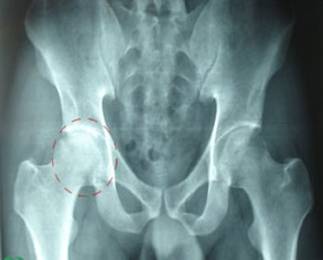

股骨頭壞死不容忽視

近日,骨關節(jié)外科門診接診了一名股骨頭壞死的患者,患者廖某因髖關節(jié)疼痛多年,行走后疼痛加重前來就診。股骨頭壞死在骨關節(jié)外科并不少見,輕者,疼痛時患者可以忍受,忍一忍就過去了。直到病情加重,才來醫(yī)院治療,往往延誤了治病的最佳時期。

股骨頭壞死,又稱股骨頭缺血性壞死,為常見的骨關節(jié)病之一。是由于多種原因導致的股骨頭局部血運不良,從而引起骨細胞進一步缺血、壞死、骨小梁斷裂、股骨頭塌陷的一種病變。